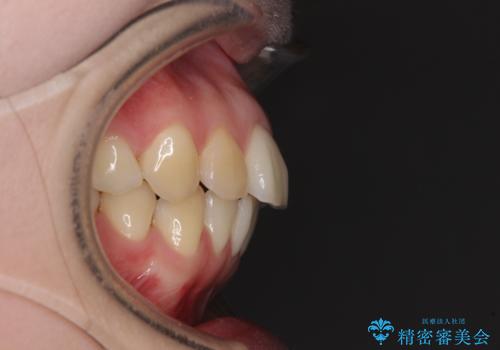

上顎骨拡大を併用したインビザライン矯正

- 上下のデコボコと奥歯の咬みにくさを気にして来院された患者様です。

上顎骨の幅が下顎骨よりも小さいので、拡大装置により骨幅を広げて上下関係を改善し、その後インビザラインにて歯並びを整えることとしました。

上下の骨幅を改善したことで、スムーズに歯列矯正を行うことができました。

矯正治療中に近医で銀歯を外す治療を開始したため、治療後に奥歯の咬み合わせが不十分ですが(こちらは近医での治療により改善するとのこと)、歯列と咬み合わせが改善され、患者様には大変満足していただきました。